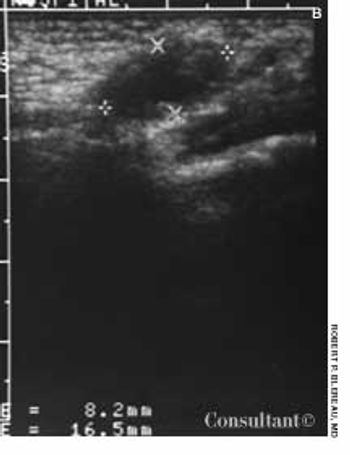

A 41-year-old man fell 3 ft into a bilge; he landed on his left leg and experienced immediate generalized pain in that knee. Three days later, he consulted his physician, who found minimal effusion in the knee and tenderness of the medial collateral ligament (MCL). No abnormalities were seen on plain x-ray films.